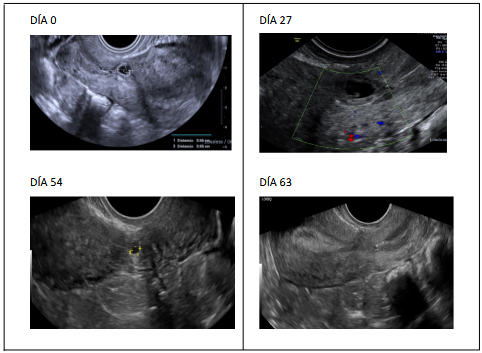

Caso 2

Paciente de 33 años actualmente con antecedente de G3P1021. Su historial obstétrico incluye una primera gestación (G1) que culminó en una cesárea, una segunda gestación (G2) que fue un aborto espontáneo, y su actúa tercera gestacupib (G3) un embarazo ectópico en cicatriz de cesárea.

En esta gestación en el día 0 (Figura 2) se realizó una ecografía que reveló un saco gestacional de 6 mm y vesícula vitelina de 2 mm. Sus niveles iniciales de HCG- β

Fueron de 2,282 Ui. Recibió dos monodosis de metotrexato intramuscular.

El día 17 tuvo ecografía con saco gestacional de 9 mm.

El día 20 tuvo HCG-β de 736 Ui.

El día 27 presenta saco gestacional de 8 mm y longitud cráneo-caudal de 2 mm sin actividad cardíaca Figura 2.

El día 54 H HCG-β negativa, ecografía: imagen quística en cicatriz de cesárea de 3x2 mm-

El día 63 Su nivel de β-hCG se confirmó en 0.1 UI (Figura 2), indicando una resolución completa del embarazo ectópico. y el día 63: HCG-β de 0.1.

Figura 2 Evolución de la imagen ecográfica del caso 2